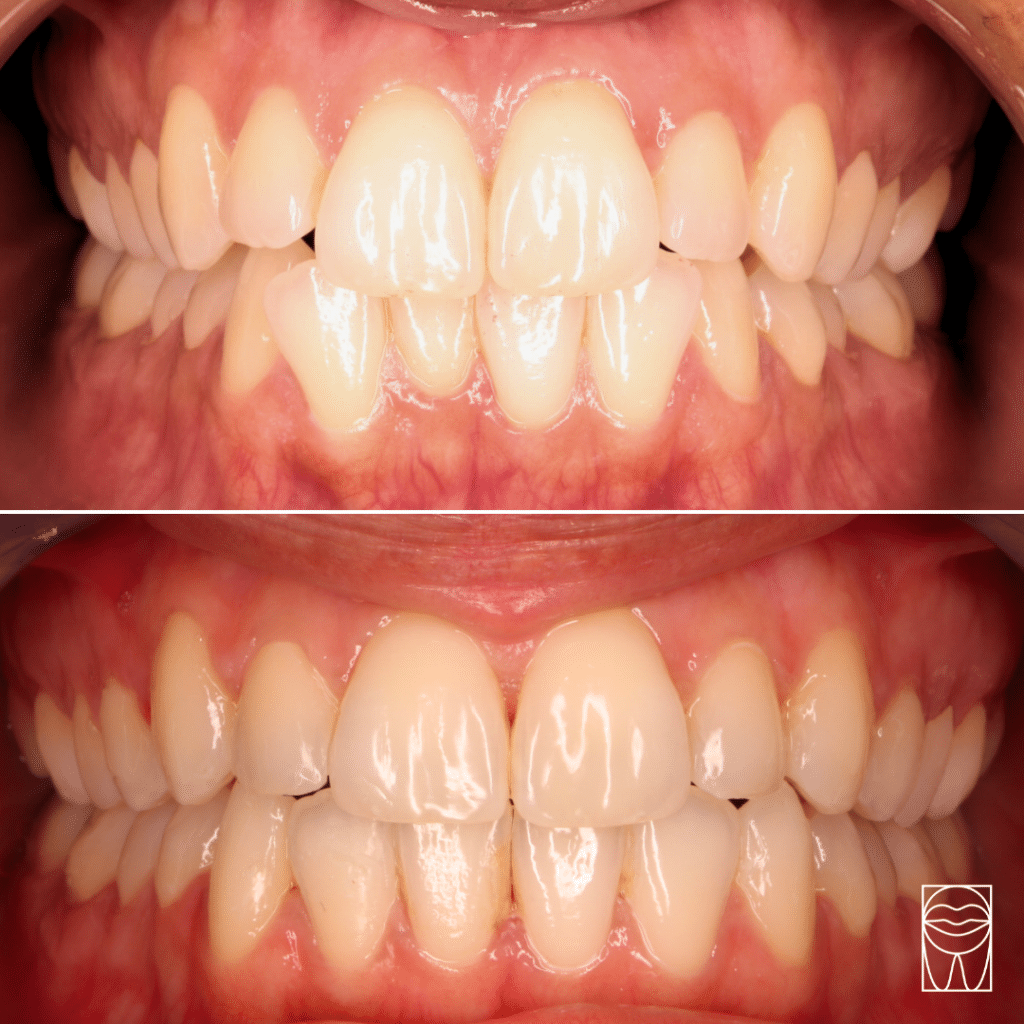

Béance

dentaire

Maloclusion

La béance dentaire : est observée lorsque la bouche est fermée, un écart anormal est présent entre les arcades supérieure et inférieure.

Nos résultats